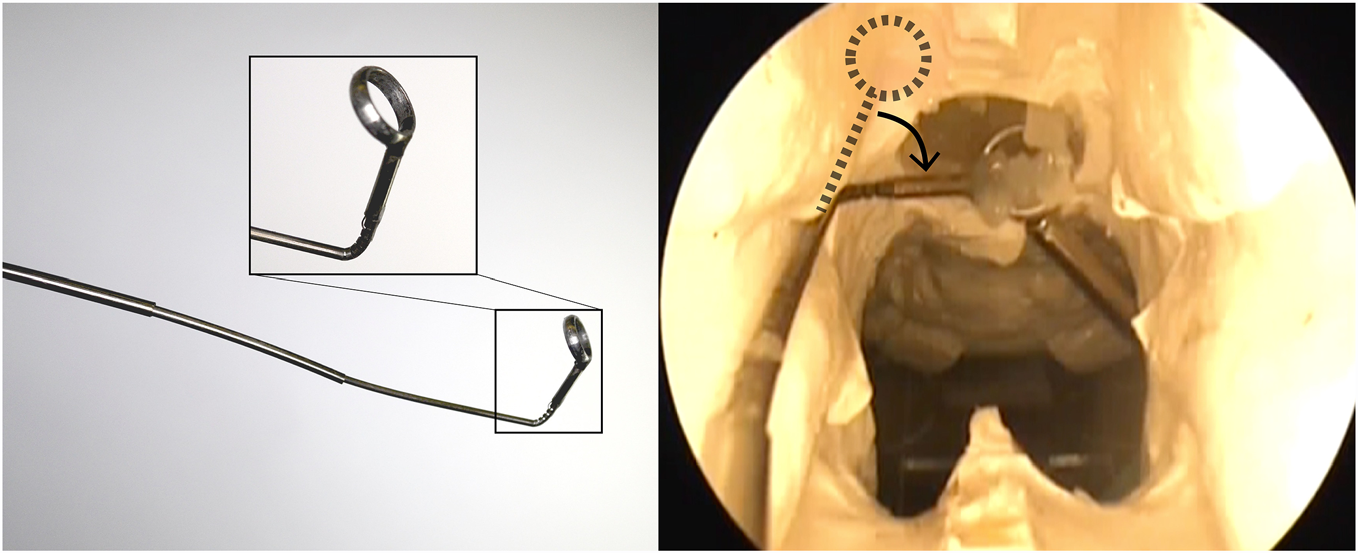

在本研究中,我们研制了一种用于针状手术工具的微型腕部,该腕部通过在镍钛合金管上加工非对称矩形切口制成,形成一个由单根肌腱驱动的柔顺弯曲区域。该腕部可装配各种手术末端执行器,用于在狭小空间内输送治疗(见图1)。我们的腕部设计最接近于参考文献[34–36]中的导管和针式设计,但其工作原理更为简单,并能实现更紧密的弯曲。我们的腕部结构易于制造,无需采用复杂的弹簧切口设计,也不依赖参考文献[34]中主动导管所使用的液压驱动。该腕部尺寸足够小,可用于针状器械,且不需要像参考文献[35]中主动导管设计所必需的镍钛合金复位弹簧。与参考文献[36]中的主动针设计相比,我们的腕部能在更小的曲率半径上实现更大的偏转角度。该腕部采用单根肌腱驱动,可通过低成本的制造方法进行原型制作。该设计具有可扩展性,能够方便地集成到针状手术工具中。

腕部最有用的特性之一是其易于集成到针状外科装置中。一种可受益于增加此类腕部的装置是同心管机器人。同心管机器人是一种针状机器人操作器,由一系列嵌套的、预弯曲的超弹性镍钛合金管组成,通常直径小于2 mm,常用于医疗应用[43]已研究将其用于前列腺切除[44]、心脏应用[45]、经鼻颅底手术[7]以及前列腺近距离放射治疗[46]。由于该腕部由镍钛合金管(与制造同心管机器人所用材料相同)制成,因此可直接在同心管机器人的最内层管上加工出腕部。这避免了需要将腕部与同心管机器人进行机械连接,从而简化了整体系统。通过使用单根肌腱驱动腕部,整个同心管机器人系统的增加的复杂性也极小。我们将该腕部集成到了参考文献[7]中提出的用于经鼻切除垂体瘤的同心管机器人中(见图17(a))。随后,我们在相同的实验装置下,通过从颅底模型模拟体中吸除明胶来验证该腕部在此手术中的应用效果(参考文献[7])。图17(b)显示了内窥镜视野下腕部偏转并将模拟肿瘤输送至吸除装置的过程。